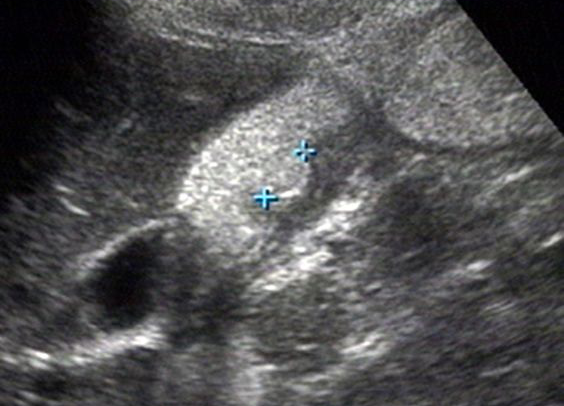

胃炎

胃造影用的是什么机子超声诊断科新技术|胃肠超声造影检查,让您舒舒服服做完肠胃筛查!_https://www.jmylbn.com_新闻资讯_第7张